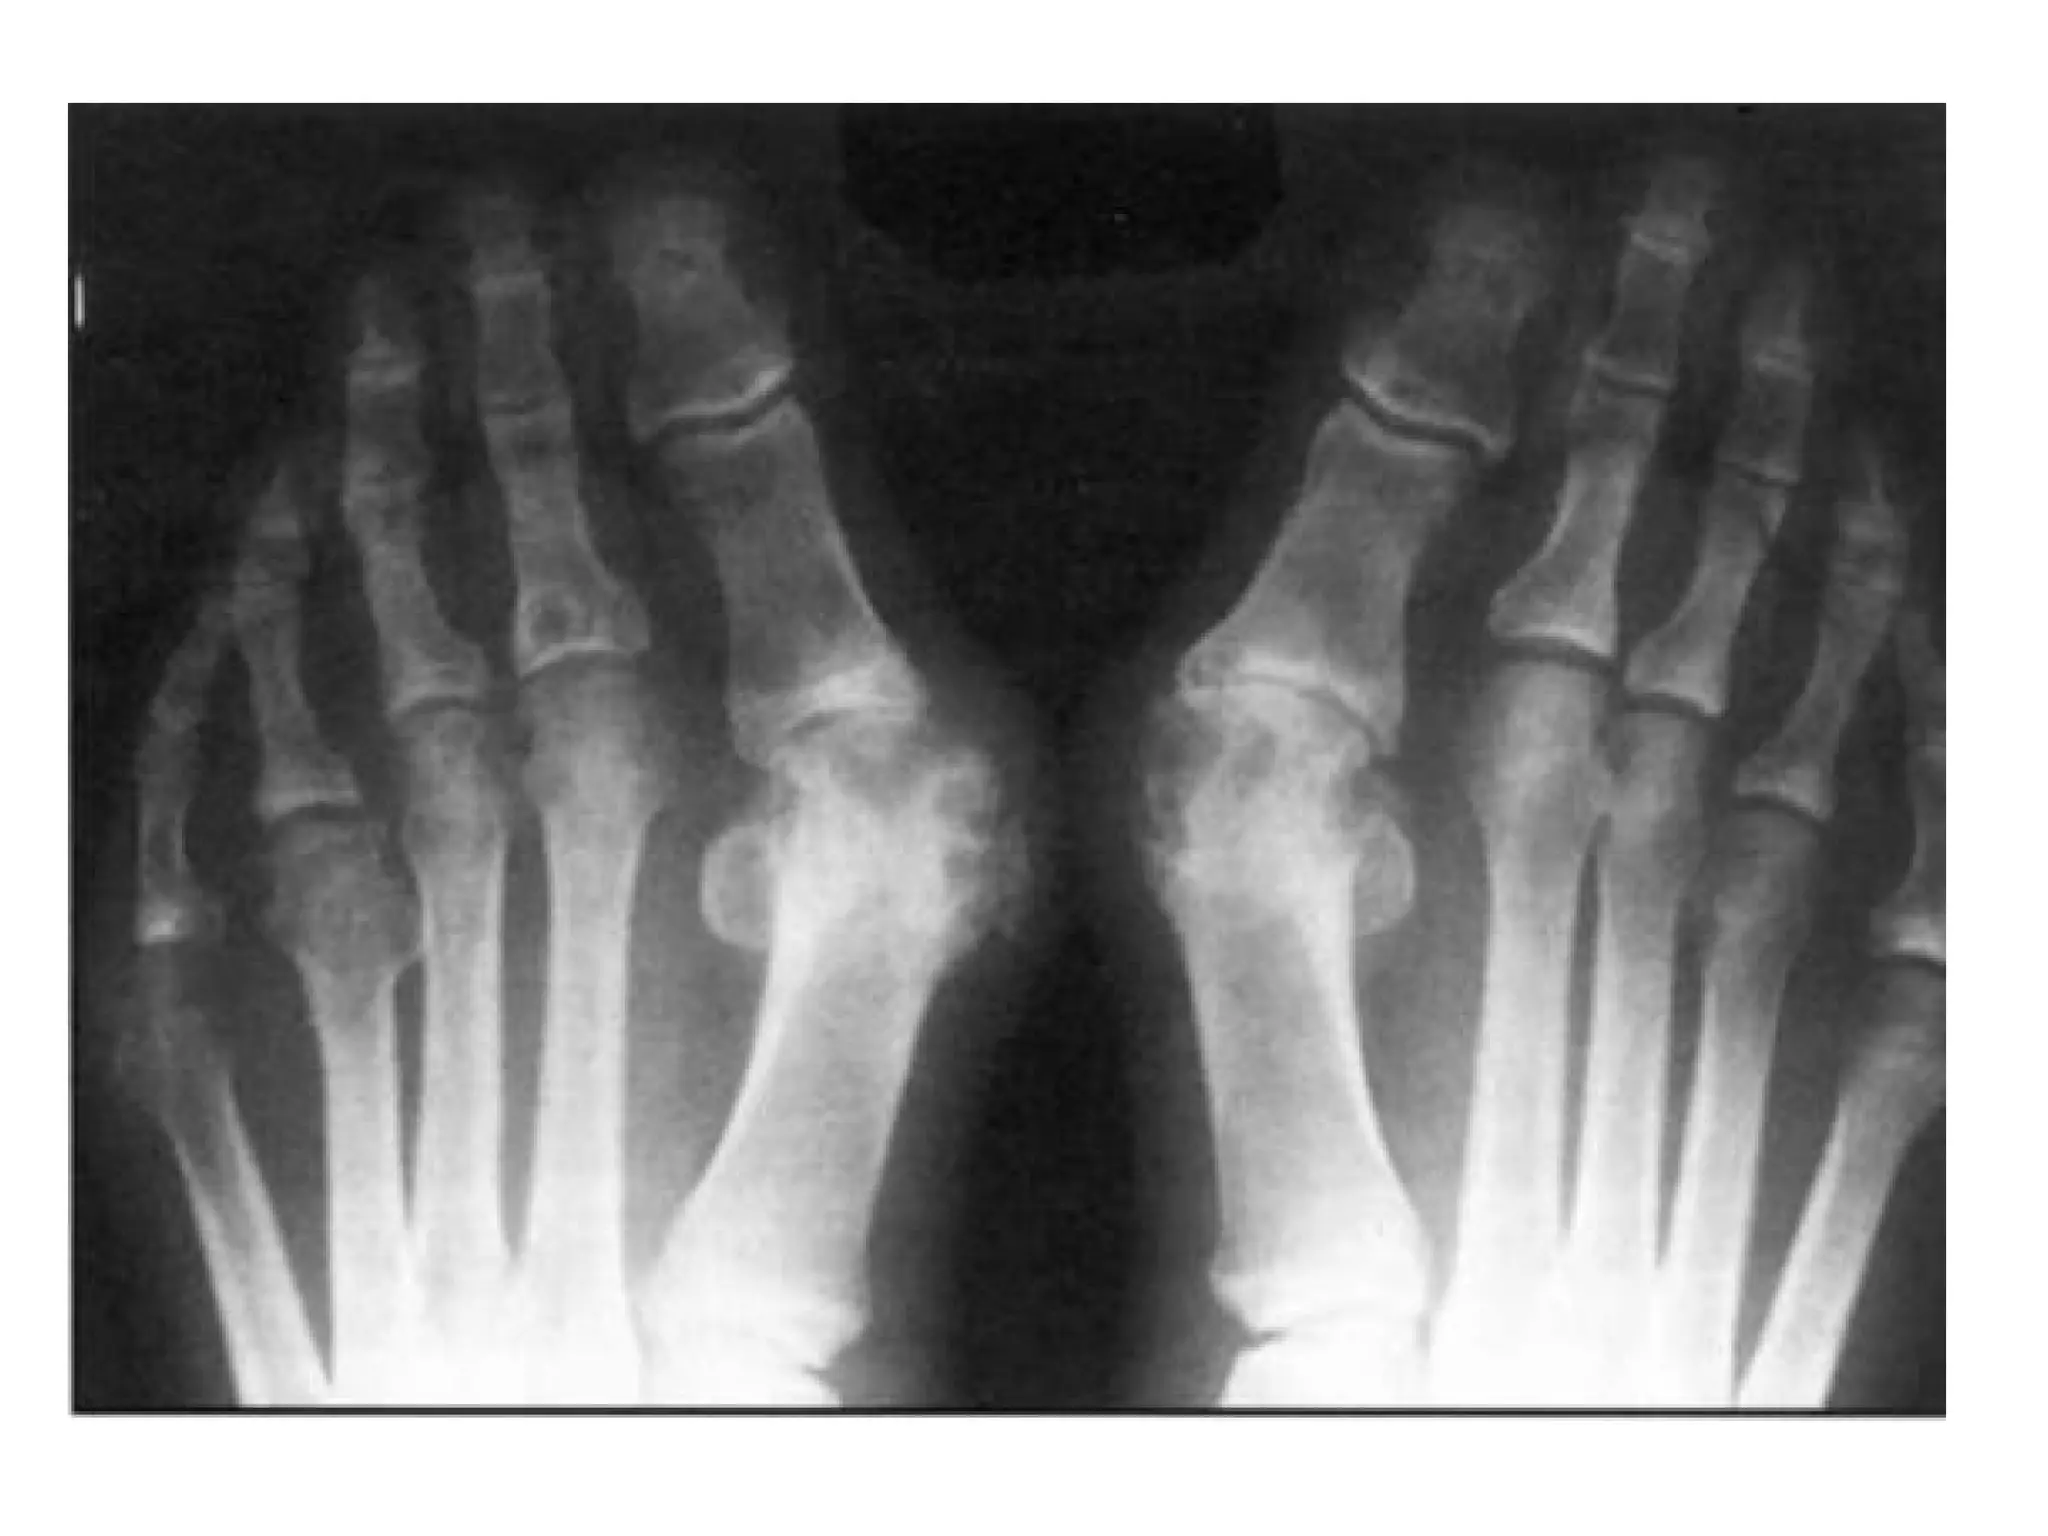

5-RA in the Feet :

-The feet are commonly involved in RA

-Typically the MTP joints in the forefoot and the

talocalcaneonavicular joint in the midfoot are

involved

-Up to 20 % of patients have the MTP joint as the

first site of involvement

Erosion of the 3rd and 5th metatarsal heads

Erosions in all the left metatarsophalangeal (MTP) joints with subluxation and valgus deformity of

most of the toes , smaller erosions in the four and fifth MTP joints of the right foot are also shown